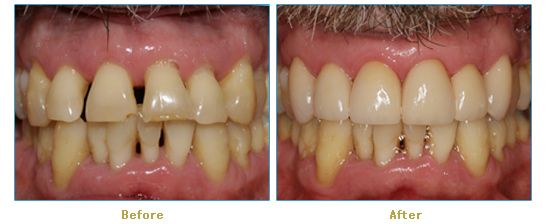

Dr. Cabianca has restored hundreds of smiles through the latest techniques in restorative and cosmetic dentistry. The following before and after photos document a few such cases in which Dr. Cabianca has replaced and reshaped teeth to produce wonderful smiles. Click on any of the images below to view larger versions of the photos.